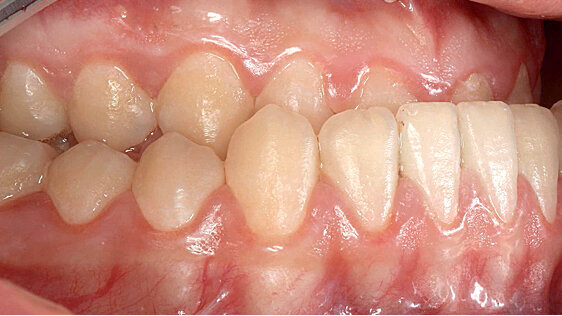

Pacientka prezentovaná v této kazuistice netrpěla nuceným progenním skusem pouze esteticky, ale také příjem potravy byl značně narušen (obr. 1a-g). Pacientka udávala, že například do jablka musela nakusovat obráceně tak, že používala dolní frontální zuby. Na bočním telerentgenovém snímku byl patrný a jasně viditelný rozsah progenie, takže v tomto případě nebude stačit pouhé posunutí dolní čelisti dozadu (obr. 2a a b).

Před začátkem terapie byl stanoven rozsah dysgnacie a s ní spojeného nuceného skusu pomocí nákusné dlahy, jež se nosí šest až osm týdnů, aby bylo možné zaručit určení fyziologické polohy kondylů. Následně proběhla ortodontická korekce v dentoalveolární oblasti, jež byla v prezentovaném případě řešitelná pouze pomocí masivního nákusu pevně fixovaného na premoláry a moláry. Nákusné dlahy umožnily odemčení zkříženého skusu ve frontě a vyklonění vpáčených řezáků v horní čelisti. Optimální pozice horní a dolní čelisti byla posouzena podle operace na modelech. Podle těchto modelů byla následně vyrobena dlaha a fixována v ústech během operace, aby bylo možné přenést předoperačně určenou fyziologickou pozici kondylů. Předoperační vyšetření pacientky ukázalo pacientku s fixními rovnátky v ústech a finální okluzí, jež byla možná jen díky masivním nákusným dlahám (obr. 4a a b). Je jasně patrné, že nákusy musely být navrženy tak, aby mohly být horní řezáky předoperačně vykloněny.